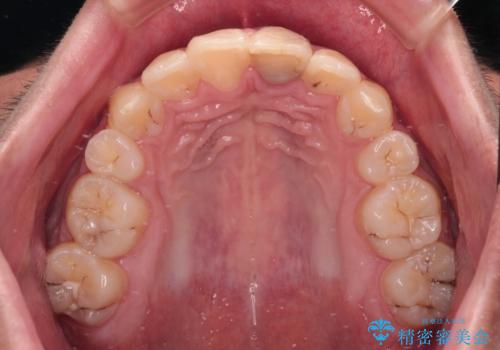

膨らんだ口元 ワイヤー装置での抜歯矯正

上下前歯が著しく前突している状態であったので、上下左右の第1小臼歯4本を抜歯し、ワイヤー装置にて矯正治療を行うこととしました。

小学生の頃に上顎前歯をぶつけ、歯の一部が破損している状態であったので、歯根が歯槽骨と癒着して移動しない可能性がありましたが、無事に治療を終えることができました。